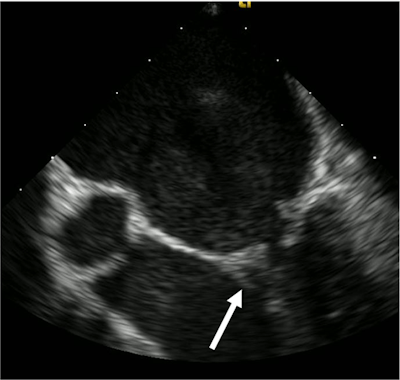

A transesophageal echocardiogram revealed vegetation, which is the hallmark of infective endocarditis, in the patient. This is believed to be the first known case of the disease stemming from robust flossing, according to the authors.

Three separate blood cultures collected 15 minutes apart yielded S. gordonii. A transthoracic echocardiogram (TTE) didn't show anything remarkable, but a transesophageal echocardiogram (TEE) revealed a small vegetation on the posterior leaflet of the mitral valve. His antibiotics were changed to 242 mg of intravenous gentamicin every 24 hours and 24 million units of penicillin G continuous infusion, due to the sensitivities of S. gordonii, the authors wrote.